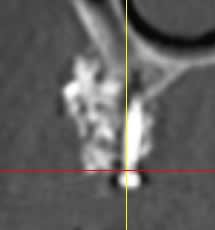

suite à divers soucis, manque d'os secteur 1, prélèvement ramique, + biooss, + vis ostéo + mbrane.

image à 6 mois

parmi les utilisateurs de biooss, avez vous déjà rencontré ce genre d'image?

et que vais je trouver ?